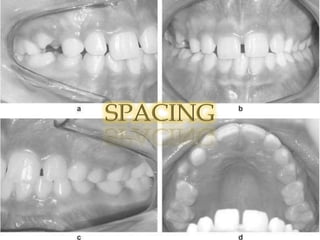

SPACING

SPACINGAetiology;1) small teeth in relation to the size of arches2) teeth are missing3) a combination of 1) and 2)! Complete space closure may be difficult and permanent retention is usually required. It may be necessary to concentrate the spaces posteriorly in the arch and fit bridges as necessary.

Management! 1) Close space.! 2) Open space and placement of a denture/ bridge.

SPACINGAetiology;1) small teethin relation to the size of arches2) teeth are missing3) a combination of 1) and 2)! Complete space closure may be difficult and permanent retention is usually required. It may be necessary to concentrate the spaces posteriorly in the arch and fit bridges as necessary.

Management! 1) Closespace.! 2) Open space and placement of a denture/ bridge.